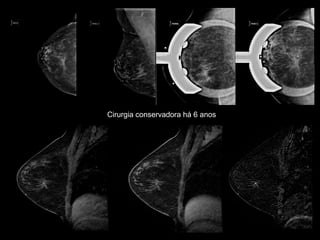

Cirurgia conservadora há 6 anos

•Determinar se achados duvidosos nos métodos convencionais tratam-se de alterações fibrocicatriciais ou de recidiva tumoral. Recidiva local

•RM é o método mais específico para diferenciar alterações fibrocicatriciais e recidiva local com VPN de 98,7% e 100% em dois estudos.

•Estimulado seu uso para identificar quais mulheres devem ou não realizar a biópsia percutânea de achados suspeitos nos métodos convencionais. Recidiva localBelli P. et al Breast Cancer Res Treat 2002; 73: 223 –235Preda L et al. Breast Cancer Res 2006, 8: R53